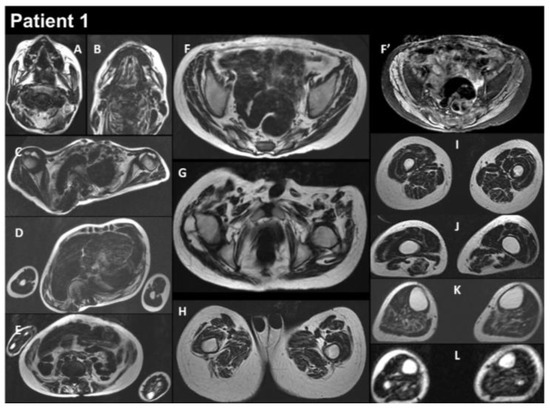

3.1. Patients’ Characteristics

| THIS STUDY | P1 | M | heteroz., de novo | RCM + myopathy | Birth | 13 y | Global | Yes | Yes | Myopathic | Normal | RCM | Restrictive respiratory syndrome | Alive at 17 y | Yes |

| P2 | M | heteroz. | HCM + myopathy | 2 y | 39 y | Global | - | Yes | - | Increased | HCM | Restrictive respiratory syndrome | Alive at 43 y | Yes | |

| P3 | F | heteroz. | HCM + myopathy | 3–4 y | 29 y | Axial and proximal | - | Yes | - | Increased | HCM | Restrictive respiratory syndrome | Alive at 34 y | Yes | |